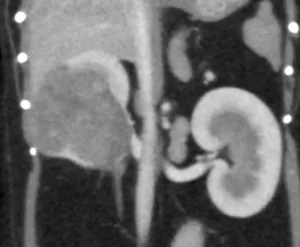

腹部超音波検査

前立腺腫瘍の拡がり、膀胱、腎臓、腰下リンパ節群を中心に評価します。

前立腺は雄犬に存在する生殖器の一部で、前立腺腫瘍の発生は稀ですが、大部分(約98%)が「腺癌」「尿路上皮癌」などの悪性腫瘍です。前立腺腫瘍の発生と去勢手術の有無には関連がないとされており、発症時点で去勢済雄が63%、未去勢雄が38%という報告があります。無症状の場合も多いですが、血尿や頻尿、排尿困難や排便困難などを認めることがあります。発見時に既に進行・転移(診断時の転移率70~80%)していることが多い腫瘍で、主な転移先としては腹腔内リンパ節、肺、骨(骨盤や腰椎)です。前立腺腫瘍が周囲に拡がることによって、尿路閉塞(尿管・尿道)や直腸狭窄を引き起こします。